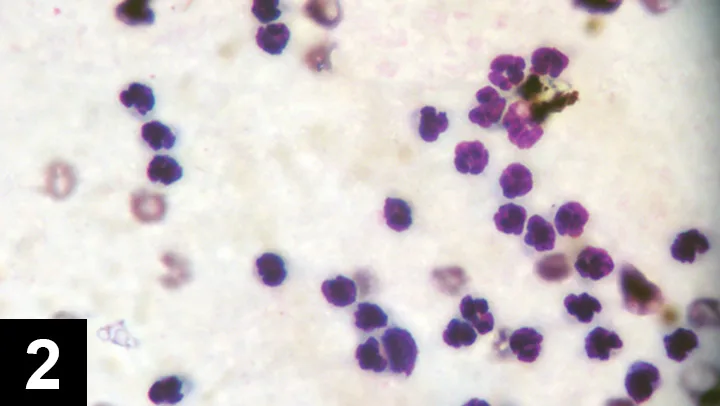

Figure 3 Cytology of joint fluid from a dog with immune-mediated polyarthritis. Note the phagocytized material representing antibody–antigen complexes. Courtesy of Dr. Anne M. Barger

If suppurative inflammation is evident in multiple joints, immune-mediated arthritis (eg, idiopathic immune-mediated polyarthritis, rheumatoid arthritis, systemic lupus erythematosus) is a leading cause. Finally, tick-borne diseases (eg, Rocky Mountain spotted fever, ehrlichiosis, Lyme disease) may also cause suppurative inflammation in single or multiple joints.